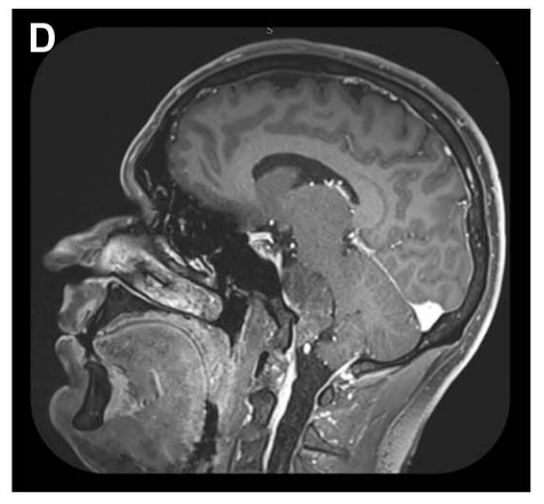

诺亚术前影像,左侧岩斜区脑膜瘤,呈不均匀强化。

而诺亚的肿瘤CT上看是个后颅窝硬膜外钙化病灶,核磁上表现为左侧岩斜区一个占位性病变,向后压迫脑干,所以福教授选择经鼻内镜手术——兵分两路:先通过血管栓塞术切断肿瘤的"粮草供应",再采用先进的单鼻孔内镜技术精准切除。

矢状位 MRI 显示肿瘤经栓塞后血供部分阻断(部分去血管化)。

具体分析:MRI诺亚术前栓塞后3D-CISS序列多平面重建 MRI,可见脑膜瘤与神经血管结构的复杂关系。